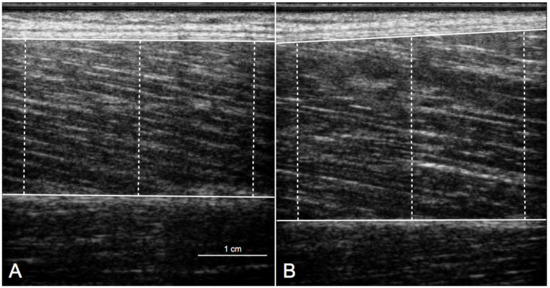

| Vastus lateralis thickness (cm) | ||||||

| All (n = 30) | 2.53 ± 0.34 | 2.62 ± 0.33 | 0.032 | −3 ± 8 | ||

| M (n = 15) | 2.60 ± 0.25 | 2.60 ± 0.27 | 0.953 | 0 ± 7 | 6 (1 to 12) | 0.021 |

| ACL + M (n = 15) | 2.47 ± 0.41 | 2.64 ± 0.40 | 0.009 | −6 ± 8 | ||